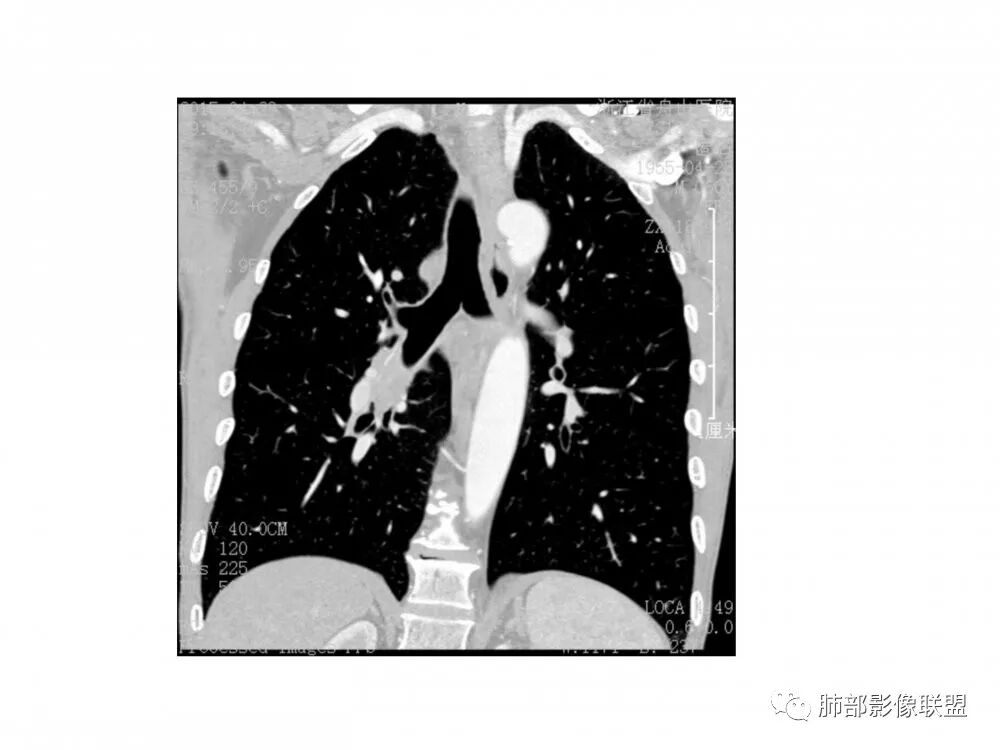

右肺下叶支气管开口新生物,轴位管腔及纵向基底干大部分受累狭窄,支气管管壁破坏明显,强化较低不均匀,肺门、7组、4R淋巴结肿大,考虑恶性支气管腔内肿瘤,鳞癌可能性大,需要与类癌、涎腺类肿瘤鉴别

男,60岁,右肺下叶支气管开口新生物,轴位管腔及纵向基底干大部分受累狭窄,支气管管壁破坏并突破形成腔外肿块,强化较低不均匀,右肺门、7组、4R淋巴结肿大,考虑恶性没问题,鳞癌可能性大,类癌、粘液表皮样癌,乳头状瘤待排。

右肺下叶支气管不规则软组织肿块,病灶沿支气管生长,有一定的张力,部分包绕支气管壁,增强病灶内可见中度强化,内部有延迟强化的特点,周围淋巴结增大,诊断恶性病变无疑,远端无明显支气管阻塞,主要考虑粘液表皮癌,腺样囊腺癌,鳞癌之间鉴别,病灶有类似神经源性病变生长方式,腺样囊腺癌,其次考虑鳞癌或粘液表皮癌。

右肺下叶支气管开口新生物,轴位管腔及纵向基底干大部分受累狭窄,支气管管壁破坏并突破形成腔外肿块,血管累及变细,肉眼观轻度强化,右肺门、纵膈淋巴结肿大,恶性没问题,阻塞性炎症不明显,类癌强化明显不支持,老年男性,首先考虑小细胞癌,鉴别不典型鳞癌和腺癌。

右肺下叶开口支气管内新生物,破坏管壁向腔外膨胀生长,累及各基底段开口,无明显坏死,有局部强化,远端无明显阻塞,右肺门及纵隔淋巴结肿大,考虑恶性肿瘤。大气道肿瘤不支持腺癌。小细胞癌大多为周围病灶引起肺门、纵隔淋巴结转移,肺门淋巴结明显肿大后侵犯支气管粘膜到达支气管内(从外到内),本例病灶从管腔内向腔外长,不支持小细胞癌。病灶为轻→中度强化,类癌显著强化为主→不支持,鳞癌、腺样囊性癌一般中度强化,鳞癌大多有阻塞性病变,本例无明显阻塞不支持鳞癌。粘液表皮样癌一般为轻度不均匀强化。感觉病灶为轻中度不均匀强化。综上首先考虑粘表,其次腺样囊性癌。待支气管镜活检明确。